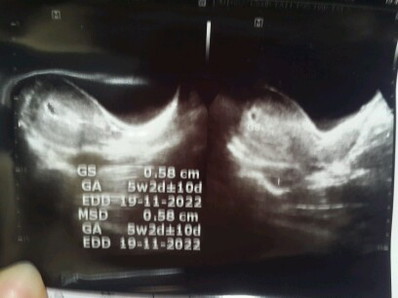

Bun Usia kandunganku menginjak 17w(hpht) kmaren priksa ke bidan tpi kebetulan bidanya lg keluar jdi hnya asisten.aku ditnya gerakanya aktif nggak ? Tapi Aku blum ngrasain gerak janinya, terus kta asistenya kok belum ngerasain ? Ini udah besar loh seharusnya udah ngrasain gerakanya. Kok aku jd khawatir ya bun. Aku memang blum usg lgi. Terakhir usg usia 5w dan 8w. Klo djj udah kedengeran pas dicek pke alatnya bidan. Ini kehamilan ke 2 saya. Yg pertama keguguran krna janin gak berkembang di usia 7w#seriusnanya #bantusharing #tanyabidan